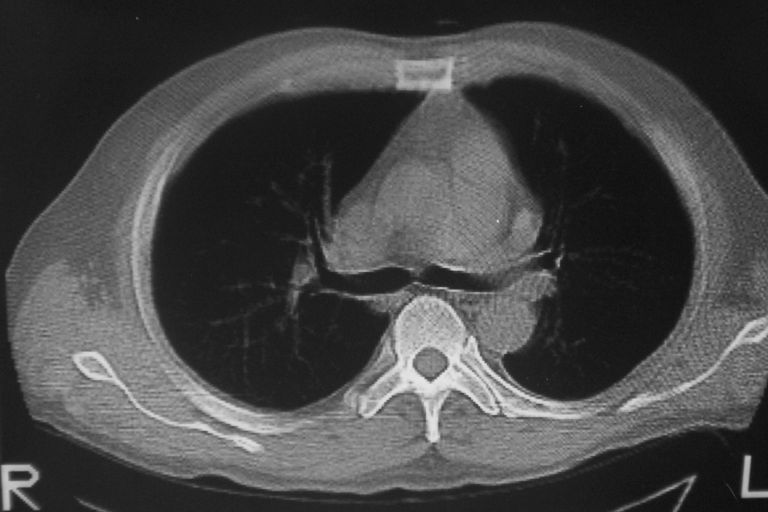

患者 男 50岁 无痛性咯血3天,无其他不适.

左下肺结节状软组织密度影,边缘有毛刺,考虑周围型肺癌。

1 左肺下叶基底段见两结节软组织密度灶, 肺窗边缘见有毛刺征像, 不能排除占位. 2 建议结合临床治疗一周后ct随访在看其结果.

临近胸膜增厚,病变周围肺不清,稍有分叶。结节密度略高,肺、纵隔窗差异不大,肺癌待排。前方还有一个

左下肺结节状软组织密度影,一个边缘有卫星病灶,邻近胸膜增厚.另一个有毛刺.心影周围水样密度影环绕.考虑:

1.肺癌可能.肺tb待排.

2.左侧胸膜增厚.心包积液.